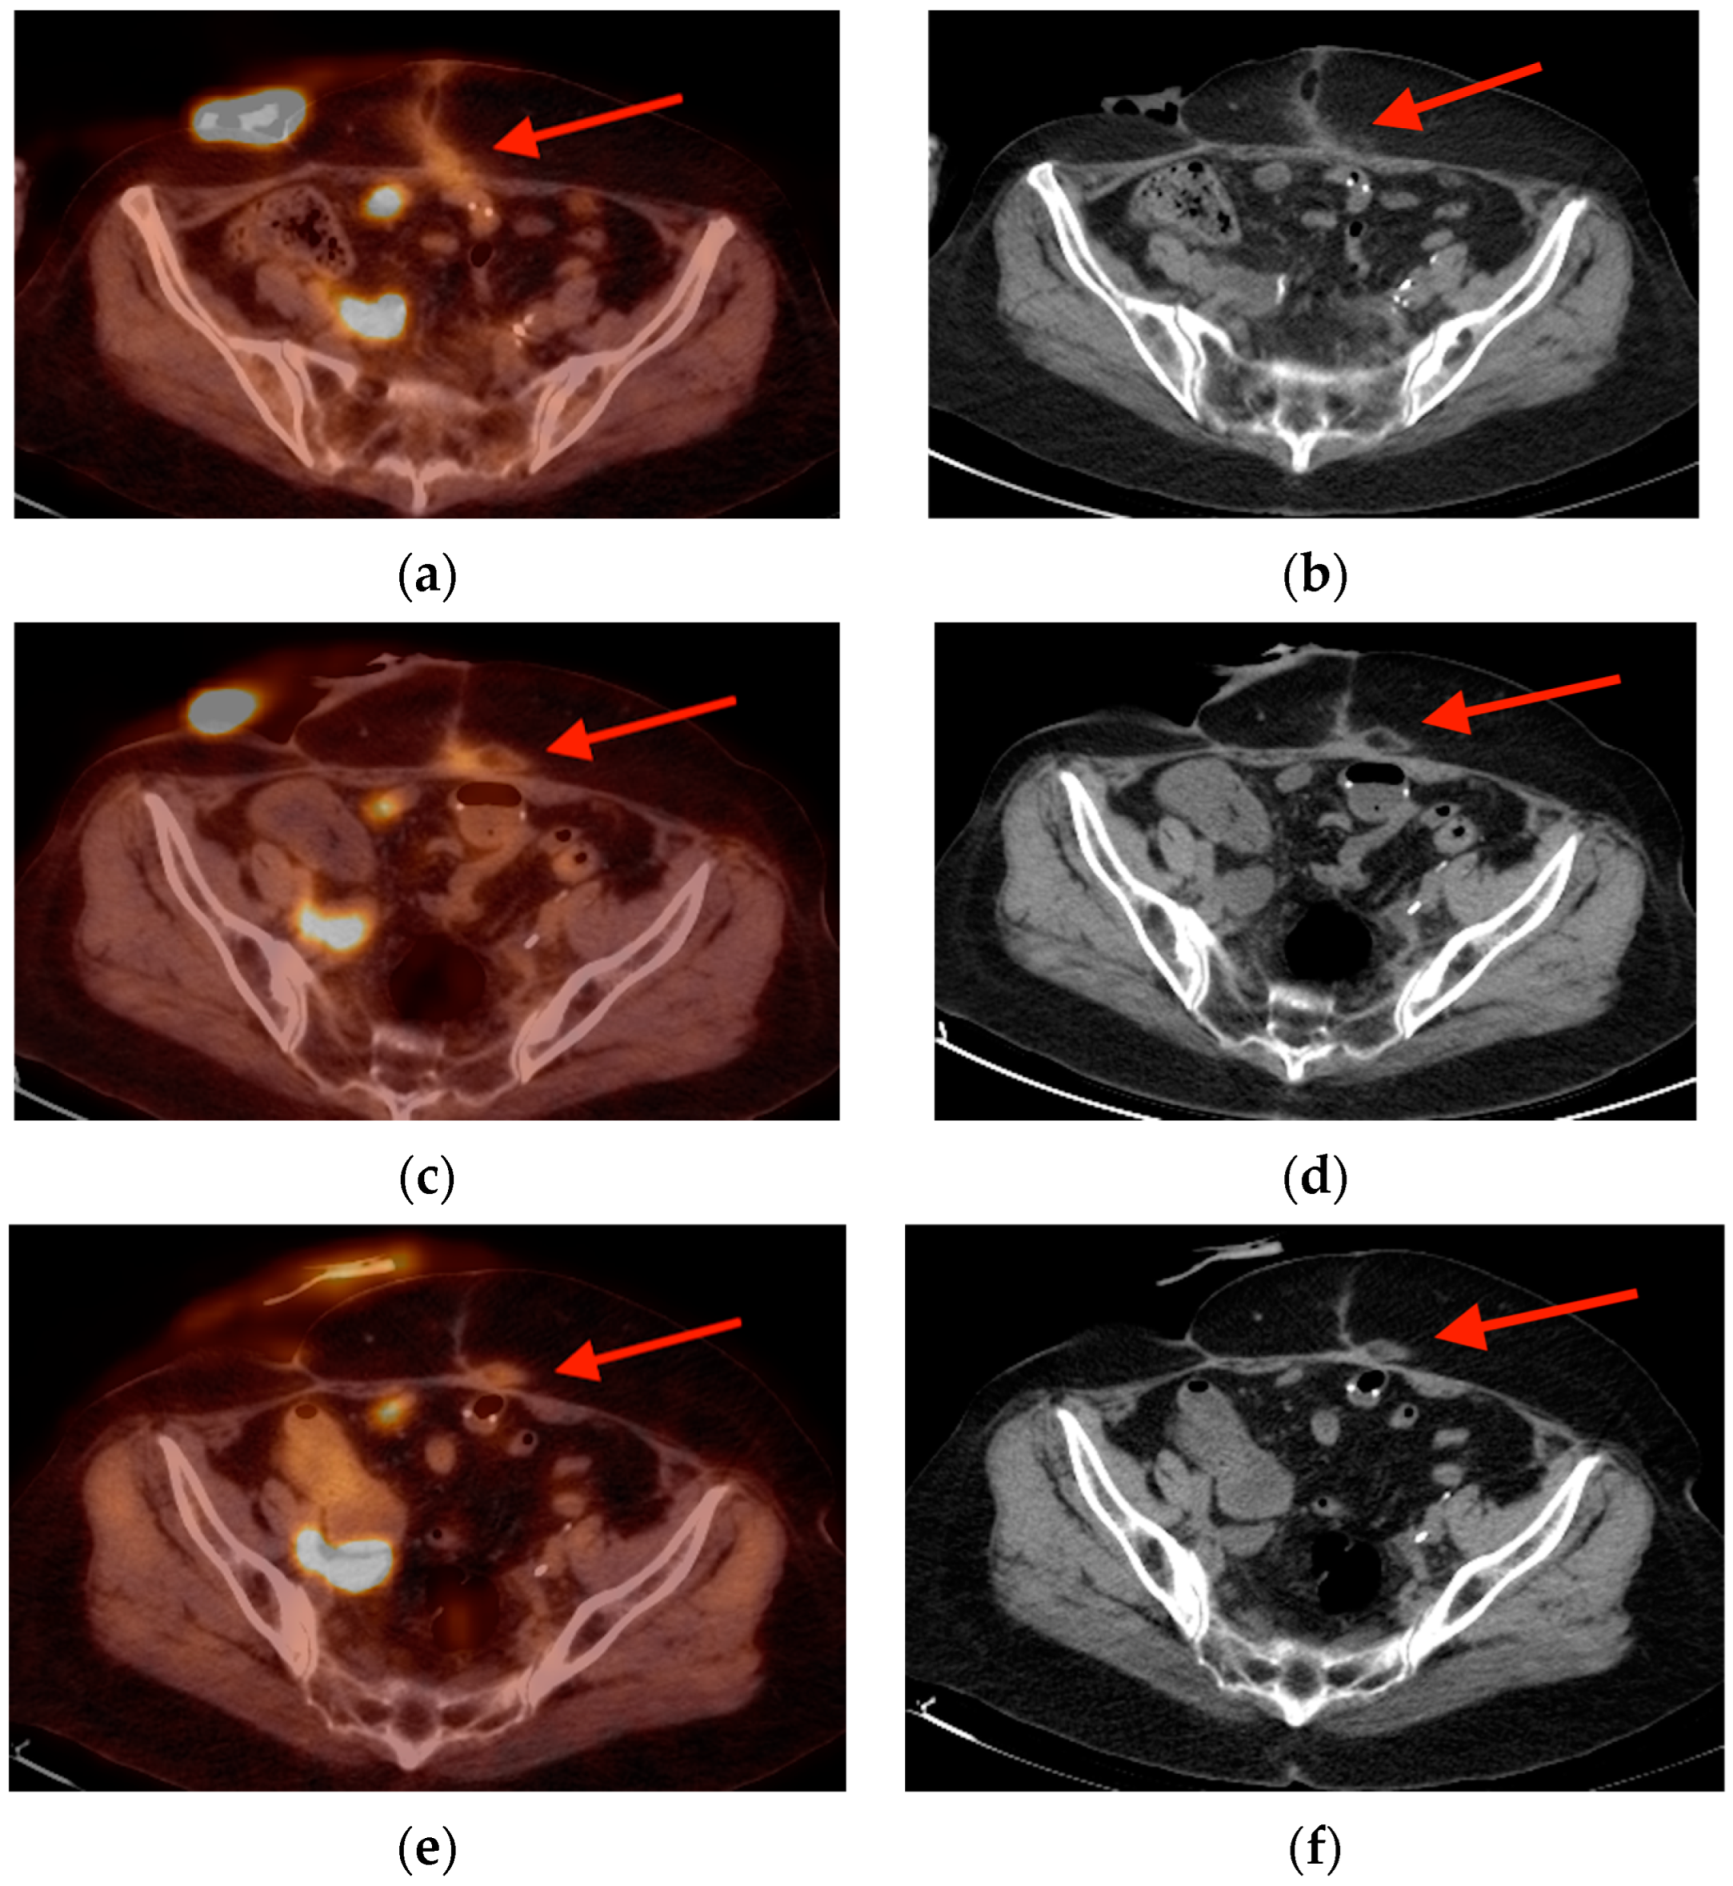

2.1. Fracture

- Oh, D.; Huh, S.J. Insufficiency fracture after radiation therapy. Radiat. Oncol. J. 2014, 32, 213–220. [Google Scholar] [CrossRef]

- Chung, Y.K.; Lee, Y.K.; Yoon, B.H.; Suh, D.H.; Koo, K.H. Pelvic Insufficiency Fractures in Cervical Cancer After Radiation Therapy: A Meta-Analysis and Review. In Vivo 2021, 35, 1109–1115. [Google Scholar] [CrossRef]

- Blomlie, V.; Rofstad, E.K.; Talle, K.; Sundfør, K.; Winderen, M.; Lien, H.H. Incidence of radiation-induced insufficiency fractures of the female pelvis: Evaluation with MR imaging. AJR Am. J. Roentgenol. 1996, 167, 1205–1210. [Google Scholar] [CrossRef]

- Abe, H.; Nakamura, M.; Takahashi, S.; Maruoka, S.; Ogawa, Y.; Sakamoto, K. Radiation-induced insufficiency fractures of the pelvis: Evaluation with 99mTc-methylene diphosphonate scintigraphy. AJR Am. J. Roentgenol. 1992, 158, 599–602. [Google Scholar] [CrossRef]

- Salavati, A.; Shah, V.; Wang, Z.J.; Yeh, B.M.; Costouros, N.G.; Coakley, F.V. F-18 FDG PET/CT findings in postradiation pelvic insufficiency fracture. Clin. Imaging 2011, 35, 139–142. [Google Scholar] [CrossRef]

- Kato, K.; Aoki, J.; Endo, K. Utility of FDG-PET in differential diagnosis of benign and malignant fractures in acute to subacute phase. Ann. Nucl. Med. 2003, 17, 41–46. [Google Scholar] [CrossRef] [PubMed]

- Shin, D.S.; Shon, O.J.; Byun, S.J.; Choi, J.H.; Chun, K.A.; Cho, I.H. Differentiation between malignant and benign pathologic fractures with F-18-fluoro-2-deoxy-D-glucose positron emission tomography/computed tomography. Skelet. Radiol. 2008, 37, 415–421. [Google Scholar] [CrossRef]

- Zhong, X.; Zhang, L.; Dong, T.; Mai, H.; Lu, B.; Huang, L.; Li, J. Clinical and MRI features of sacral insufficiency fractures after radiotherapy in patients with cervical cancer. BMC Womens Health 2022, 22, 166. [Google Scholar] [CrossRef]